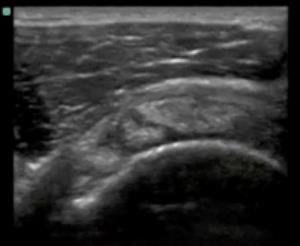

冈上肌前侧全层撕裂图像